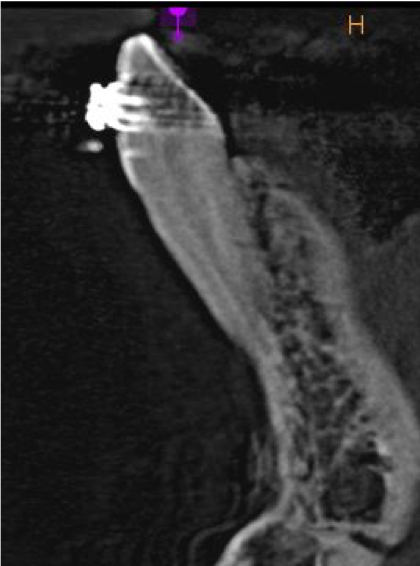

Pacjentka wiek: 26 l.

Badanie z dnia: 19.02.2019

CBCT wycinkowe żuchwy.

Pacjentka w trakcie leczenia chirurgicznego -płytka i śruby w okolicy bródkowej oraz ortodontycznego.

Zęby poddawane mechanoterapii ortodontycznej wykazują zmiany:

Ząb 31 zaawansowana resorpcja wewnętrzna prowadząca do zmniejszenia grubości struktur zęba a tym samym obniżenia jego wytrzymałości .W obrazie widoczne złamania patologiczne korzenia -szczeliny złamania przechodzące na poziomie ogniska resorpcyjnego.